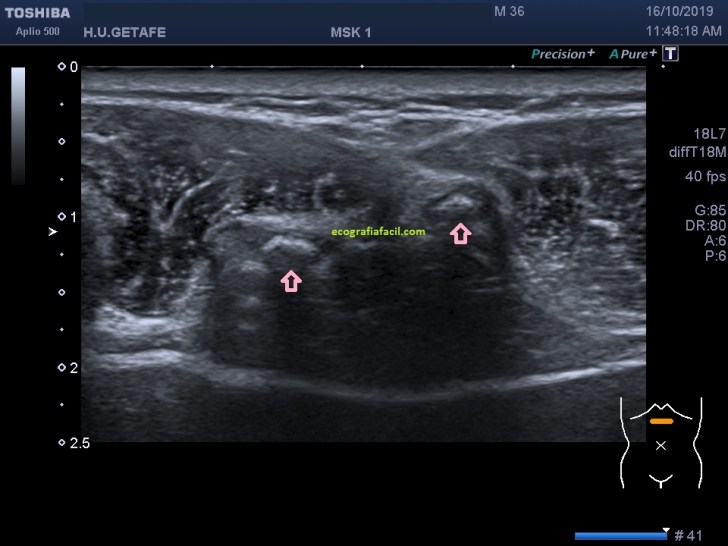

En la imagen 2 se observan claramente dos líneas que se angulan hacia anterior. Esas dos imágenes, ecográficamente corresponden a la imagen 3…

Se evidencia una imagen donde el apéndice xifoides parece terminar en dos, bífido. Lo puedes apreciar como dos imágenes hiperecogénicas señaladas con flecha rosa, a niveles distintos, la izquierda más anterior que la derecha. En el corte longitudinal de ambas terminaciones observamos esto (imagen 4 y 5)

En la imagen 4 y 5, marcado por flechas rojas, ves ambas terminaciones, observa en las imágenes la angulación de la sonda en un corte parasagital para poder ver en toda su longitud dicha terminación en cada uno de los lados.

Se trata de certificar ecográficamente que el «bulto» que se toca el paciente tan solo es una formación «rara» del Apéndice Xifoides y no una patología. No es extraño ver este tipo de consultas.

Observar que las partes blandas de la zona no estén cambiadas ecoarquitectónicamente, que la semiología de las diferentes estructuras sea acorde a la normalidad, desde el tejido óseo pasando por la musculatura y la grasa, hará que el informe radiológico sea favorable, en condiciones normales, no hay que realizar más pruebas.